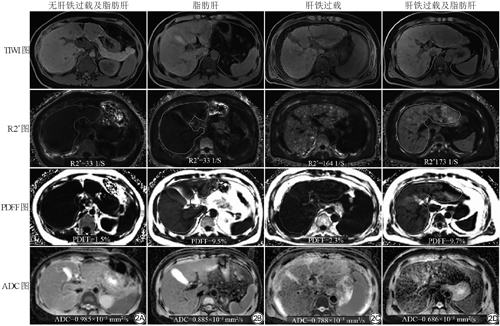

对比非肝铁过载组,肝铁过载组的ADC值显著降低[(0.893±0.054)×10-3 mm2/s与(0.842±0.098)×10-3 mm2/s,t=-2.807,P=0.007];组间年龄、性别、AST、ALT、PLT及APRI的差异均无统计学意义(P>0.05)。对比非脂肪肝组,脂肪肝组的ADC值也显著降低[(0.878±0.083)×10-3 mm2/s与(0.820±0.074)×10-3 mm2/s,t=-2.522,P=0.014] (图1);组间年龄、性别、AST、ALT、PLT及APRI的差异均无统计学意义(P>0.05)。图2显示肝铁过载或(和)脂肪肝患者的ADC值降低。

有无肝铁、脂肪沉积的患者ADC图的信号对比。对比无肝铁过载及脂肪肝的患者(A),脂肪肝(B)、肝铁过载(C)和肝铁过载及脂肪肝(D)的患者ADC图的信号不同程度降低

Comparison of ADC map signals in patients with or without hepatic iron and fat deposits. Compared to patients without hepatic iron overload and fatty liver (A), patients with fatty liver (B), hepatic iron overload (C), and hepatic iron overload and fatty liver (D) have differentially reduced signals in ADC maps.